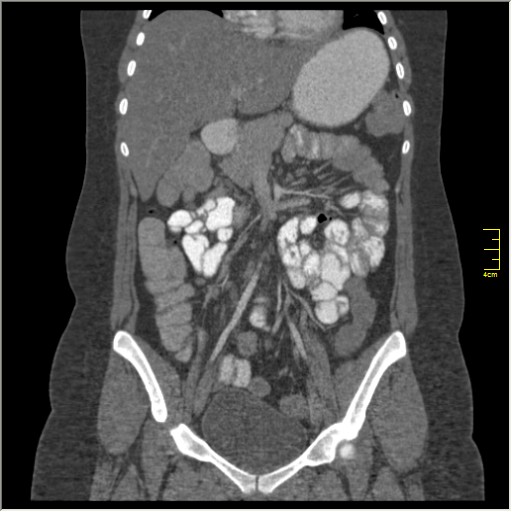

КТ энтерография

Демонстрационные изображение, оцените возможности метода! Толщина среза реконструкции 0.5-1 мм.